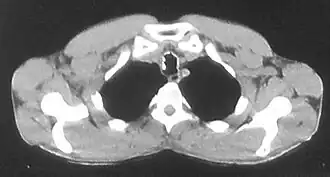

Изображение трахеи с включениями хрящевой и костной плотности по ходу её стенок при остеохондропластической трахеобронхопатии | |

При компьютерной томографии выявляются цепочки выступающих в просвет дисковидных включений хрящевой и костной плотности по ходу стенок трахеи и бронхов с деформацией и сужением просвета всей дыхательной трубки или отдельных её сегментов в хрящевой части[2][8][17][23][25][26].